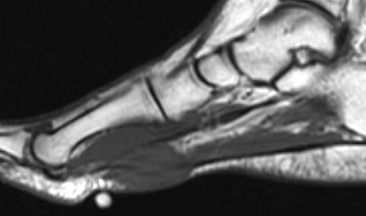

MRI

Focal oval shaped lesions within the plantar fascia